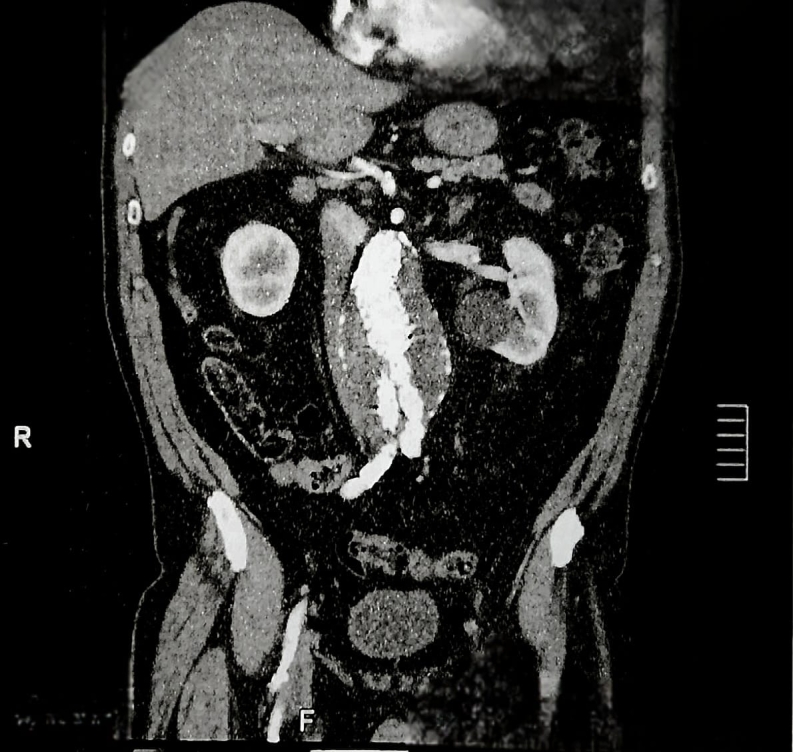

III型内漏的特点是内接枝结构出现问题,如金属结构断裂、分离或破裂。它们是一种罕见的并发症,在经血管内修复治疗腹主动脉瘤的患者中发生率为2.1%,在第一代和第二代内移植物中发病率较高,可早发生(30天后),也可晚发生。这种类型分为IIIa -组件模块化分离-和IIIb -涉及内移植物的网状骨折或破裂。本病例报告描述了一位无症状的患者,他之前接受了肾下腹主动脉瘤修复术,并在随访的计算机断层扫描中发现了一个IIIa型内漏,主体与近端延伸分离。进行第二次血管内介入以封闭腔内渗漏并矫正动脉瘤。

Type III endoleaks are characterized by a problem with the endograft structure, such as fracture of the metallic structure, separation, or rupture. They constitute a rare complication, occurring in 2.1% of patients after treatment of abdominal aortic aneurysm by endovascular repair, with higher incidence in first and second generation endografts, and can occur early (after 30 days) or later. This type III classification is subdivided into IIIa -modular separation of components - and IIIb - mesh fracture or rupture involving the endograft. This case report describes an asymptomatic patient who had previously undergone infrarenal abdominal aortic aneurysm repair and underwent follow-up computed tomography which found a type IIIa endoleak with separation of the main body from the proximal extension. A second endovascular intervention was performed to seal the endoleak and correct the aneurysm.